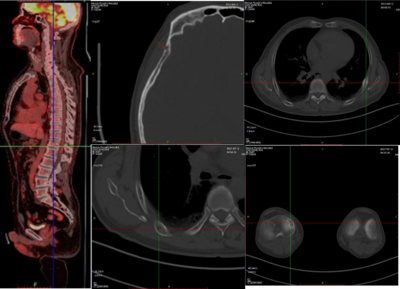

医生会通过一系列影像学检查来精确评估骨骼的受损情况:

3.PET-CT:不仅能清晰地显示骨骼的结构损伤,还能通过代谢活性判断哪些病灶是“活跃”的,对于分期、疗效评估和预后判断具有极高价值。